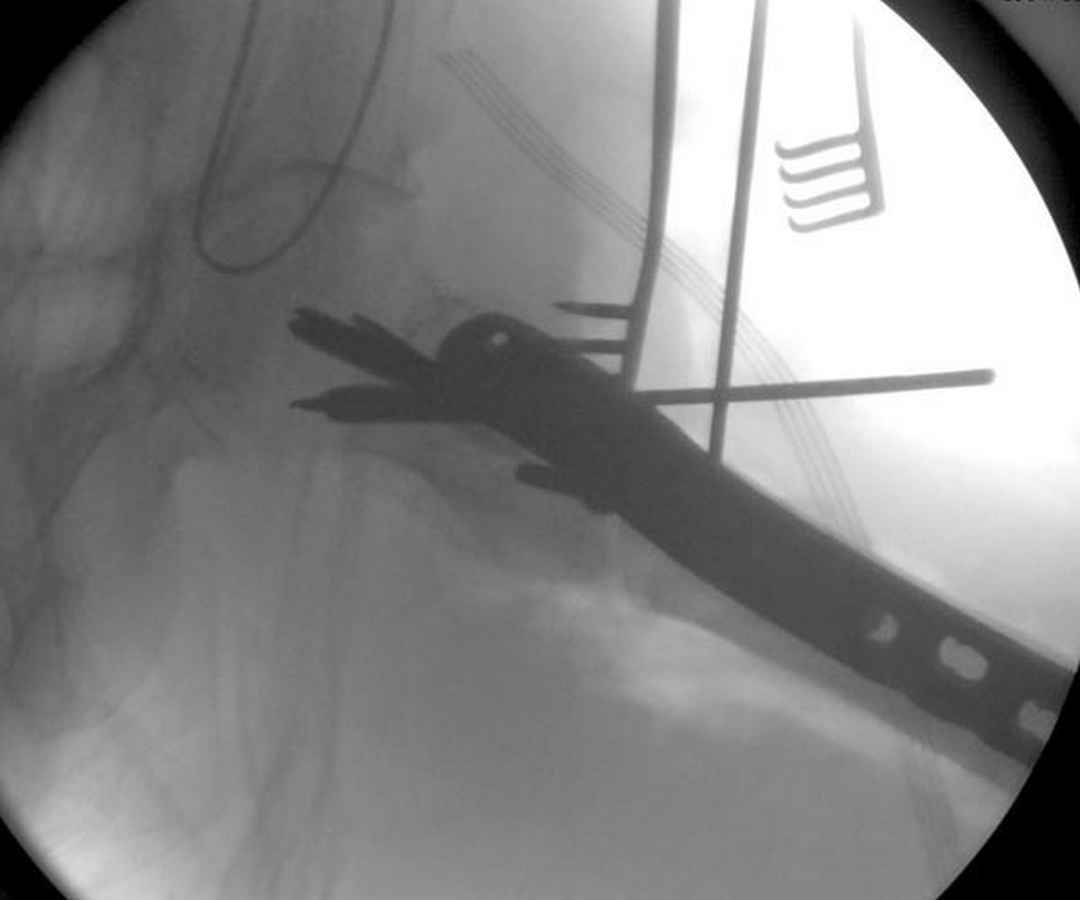

Здесь 83 года, травма в результате падения

Djoldas Kuldjanov, M.D.

Department of Orthopedic Surgery

St. Louis University

судя по картинкам с ЭОПа явно использовались приемы непрямой репозиции под его контролем, а так же интраоперационный ЭОП-контроль положения винтов, без такого контроля операция может ухудшить ситуацию (опять же учтите сроки) т.к. результат буде зависеть в большей степени от искусства хирурга, а не от технологии